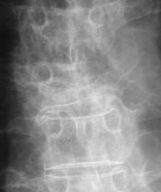

Quel est votre diagnostic ?

Il s'agit d'une fracture vertébrale maligne : vertèbre borgne par disparition d'un pédicule. Sur les radiographies standard, les caractéristiques d'une fracture d'origine bénigne doivent être vérifiées : elle ne siège jamais au-dessus de la 4e vertèbre dorsale, et en particulier au rachis cervical; les plateaux sont fracturés et non lysés ; il n'existe pas de lacune ostéolytique ; le mur et l'arc postérieurs sont intacts (les 2 pédicules sont bien vus sur les clichés de face) ; il n'y a pas d'aspect anormal des parties molles. Un doute sur une seule de ces caractéristiques doit évoquer l'origine maligne.